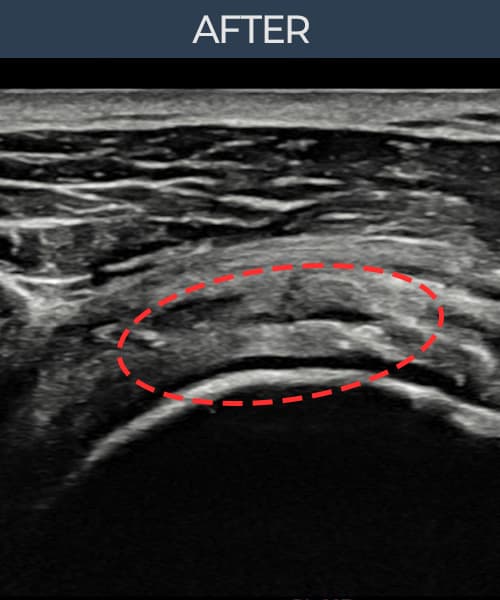

시술 전 초음파 측정 결과 파열 크기는 8mm × 5mm (힘줄 두께의 약 45% 결손)로 확인되었습니다. 시술 전 초음파에서 관절면측 회전근개 부착부의 두께 감소와 힘줄-뼈 접합부의 에코 불균질성이 뚜렷하게 관찰되었습니다. 시술 후 초음파에서 부착부 두께가 유의하게 증가하였고, 힘줄 내부의 에코 패턴이 균질하게 회복되었습니다.

40대 중반 여성 환자분으로, 두 아이를 키우며 집안일을 혼자 도맡아 하시는 분이었습니다. 빨래 널기, 높은 곳 정리 등 팔을 위로 올리는 동작에서 통증이 반복되다 점차 일상적인 동작에서도 통증이 생겨 내원하셨습니다. 초음파 검사에서 관절면측 회전근개 부착부의 두께 감소와 부분파열이 확인되었으며, 비수술 축소봉합술로 인대-뼈 부착부를 고정하는 치료 계획을 수립하였습니다. 시술은 30여 분 만에 완료되었고 당일 귀가하셨으며, 시술 후 2주째부터 가벼운 생활 동작을 단계적으로 허용하였습니다. 6주 후 추적 초음파에서 봉합 위치가 안정적으로 유지됨을 확인하였고, 최종 경과 관찰에서 부착부 두께가 유의하게 증가하여 통증 없이 가사 활동이 가능해지셨습니다.